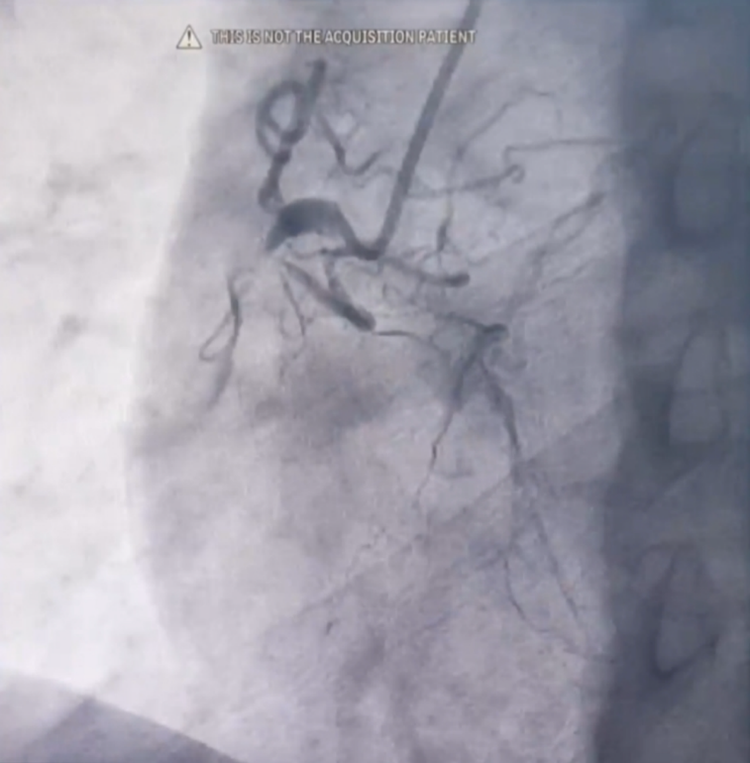

Người bệnh được chỉ định chụp động mạch vành qua hệ thống máy chụp mạch máu số hoá xoá nền (DSA), kết quả cho thấy tắc hoàn toàn cả 3 nhánh động mạch vành, đặc biệt các mạch tắc được nuôi dưỡng bằng mạch tuần hoàn bàng hệ từ chính những nhánh tắc.

| Tắc hoàn toàn động mạch vành phải) Tắc hoàn toàn động mạch mũ bên trái |